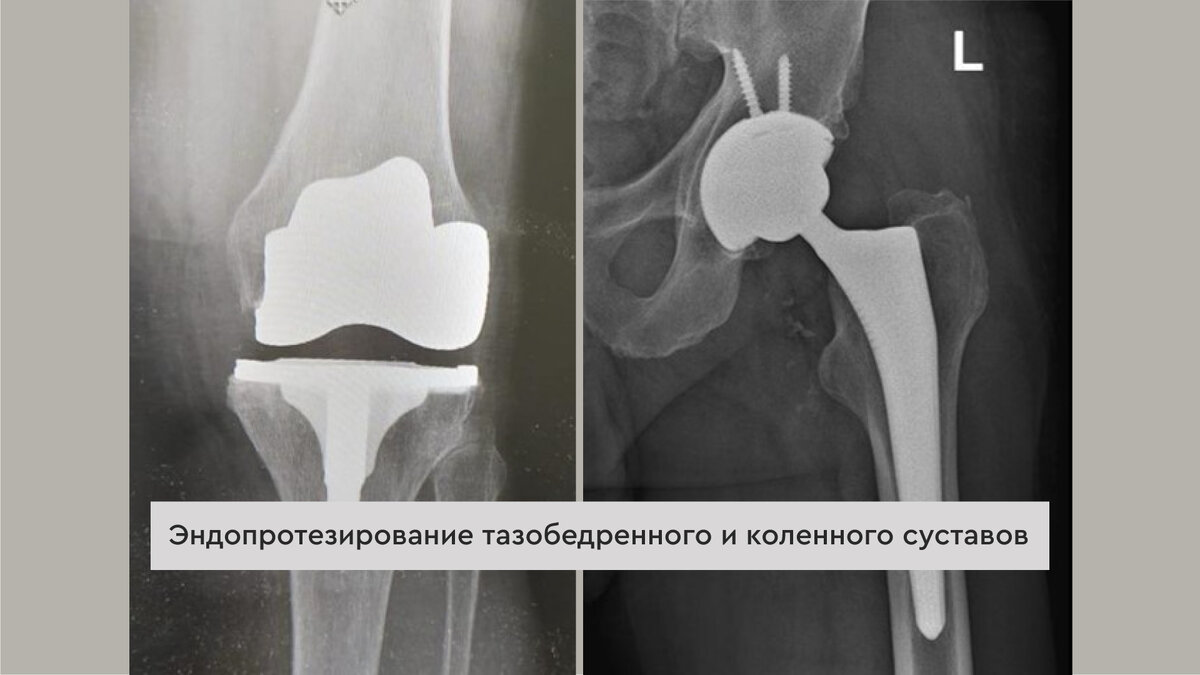

Эндопротезирование тазобедренного и коленного суставов

Операция по установке эндопротеза помогает убрать болевой синдром и вернуть подвижность коленному суставу за счет устранения деформации. Эндопротез выполнен в точности как обычный коленный сустав и позволяет совершать необходимую амплитуду движений.

Эндопротез тазобедренного сустава состоит из ножки, которая устанавливается в бедренную кость и её головки, а также чашки с её вкладышем, которая устанавливается в вертлужную впадину. Такое соединение обеспечивает движения в разных направлениях, соответствующие здоровому суставу.